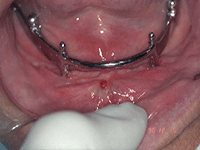

| Figure 1: Subperiosteal design dental implants | ||

Commercial dental implants came to the United States in 1940 with Gustavo Dahl presenting the first dental implants—a subperiosteal design (Figure 1). Dental implants have undergone various transformations in design, shape architecture, and metallurgy or component constituency. Currently, hundreds of different designs and components exist. Since their inception in 1940, implants have changed from the subperiosteal design to blade-type or endosteal implants invented by Dr. Leonard Linkow of New York (Figure 2), to modern screw-type implants (Figure 3) and mini implants (Figure 4), with each type promoting different restorative options in the field of dental implantology. All of these, when located in unknown remains, can provide a useful tool for the forensic dentist as a possible piece of the puzzle in the identification protocol.